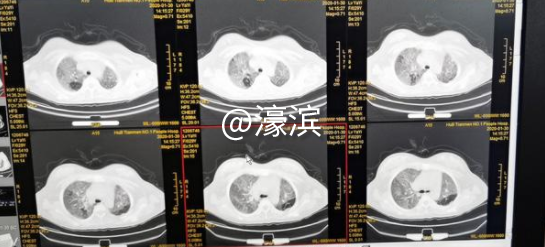

李青的肺部CT。